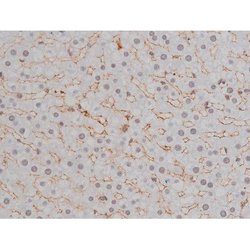

Invitrogen™ Phospho-NPM1 (Thr199) Polyclonal Antibody

Antibody detects endogenous levels of Nucleophosmin only when phosphorylated at Threonine 199.

| Applications | Immunohistochemistry (Paraffin), Western Blot, Immunocytochemistry |